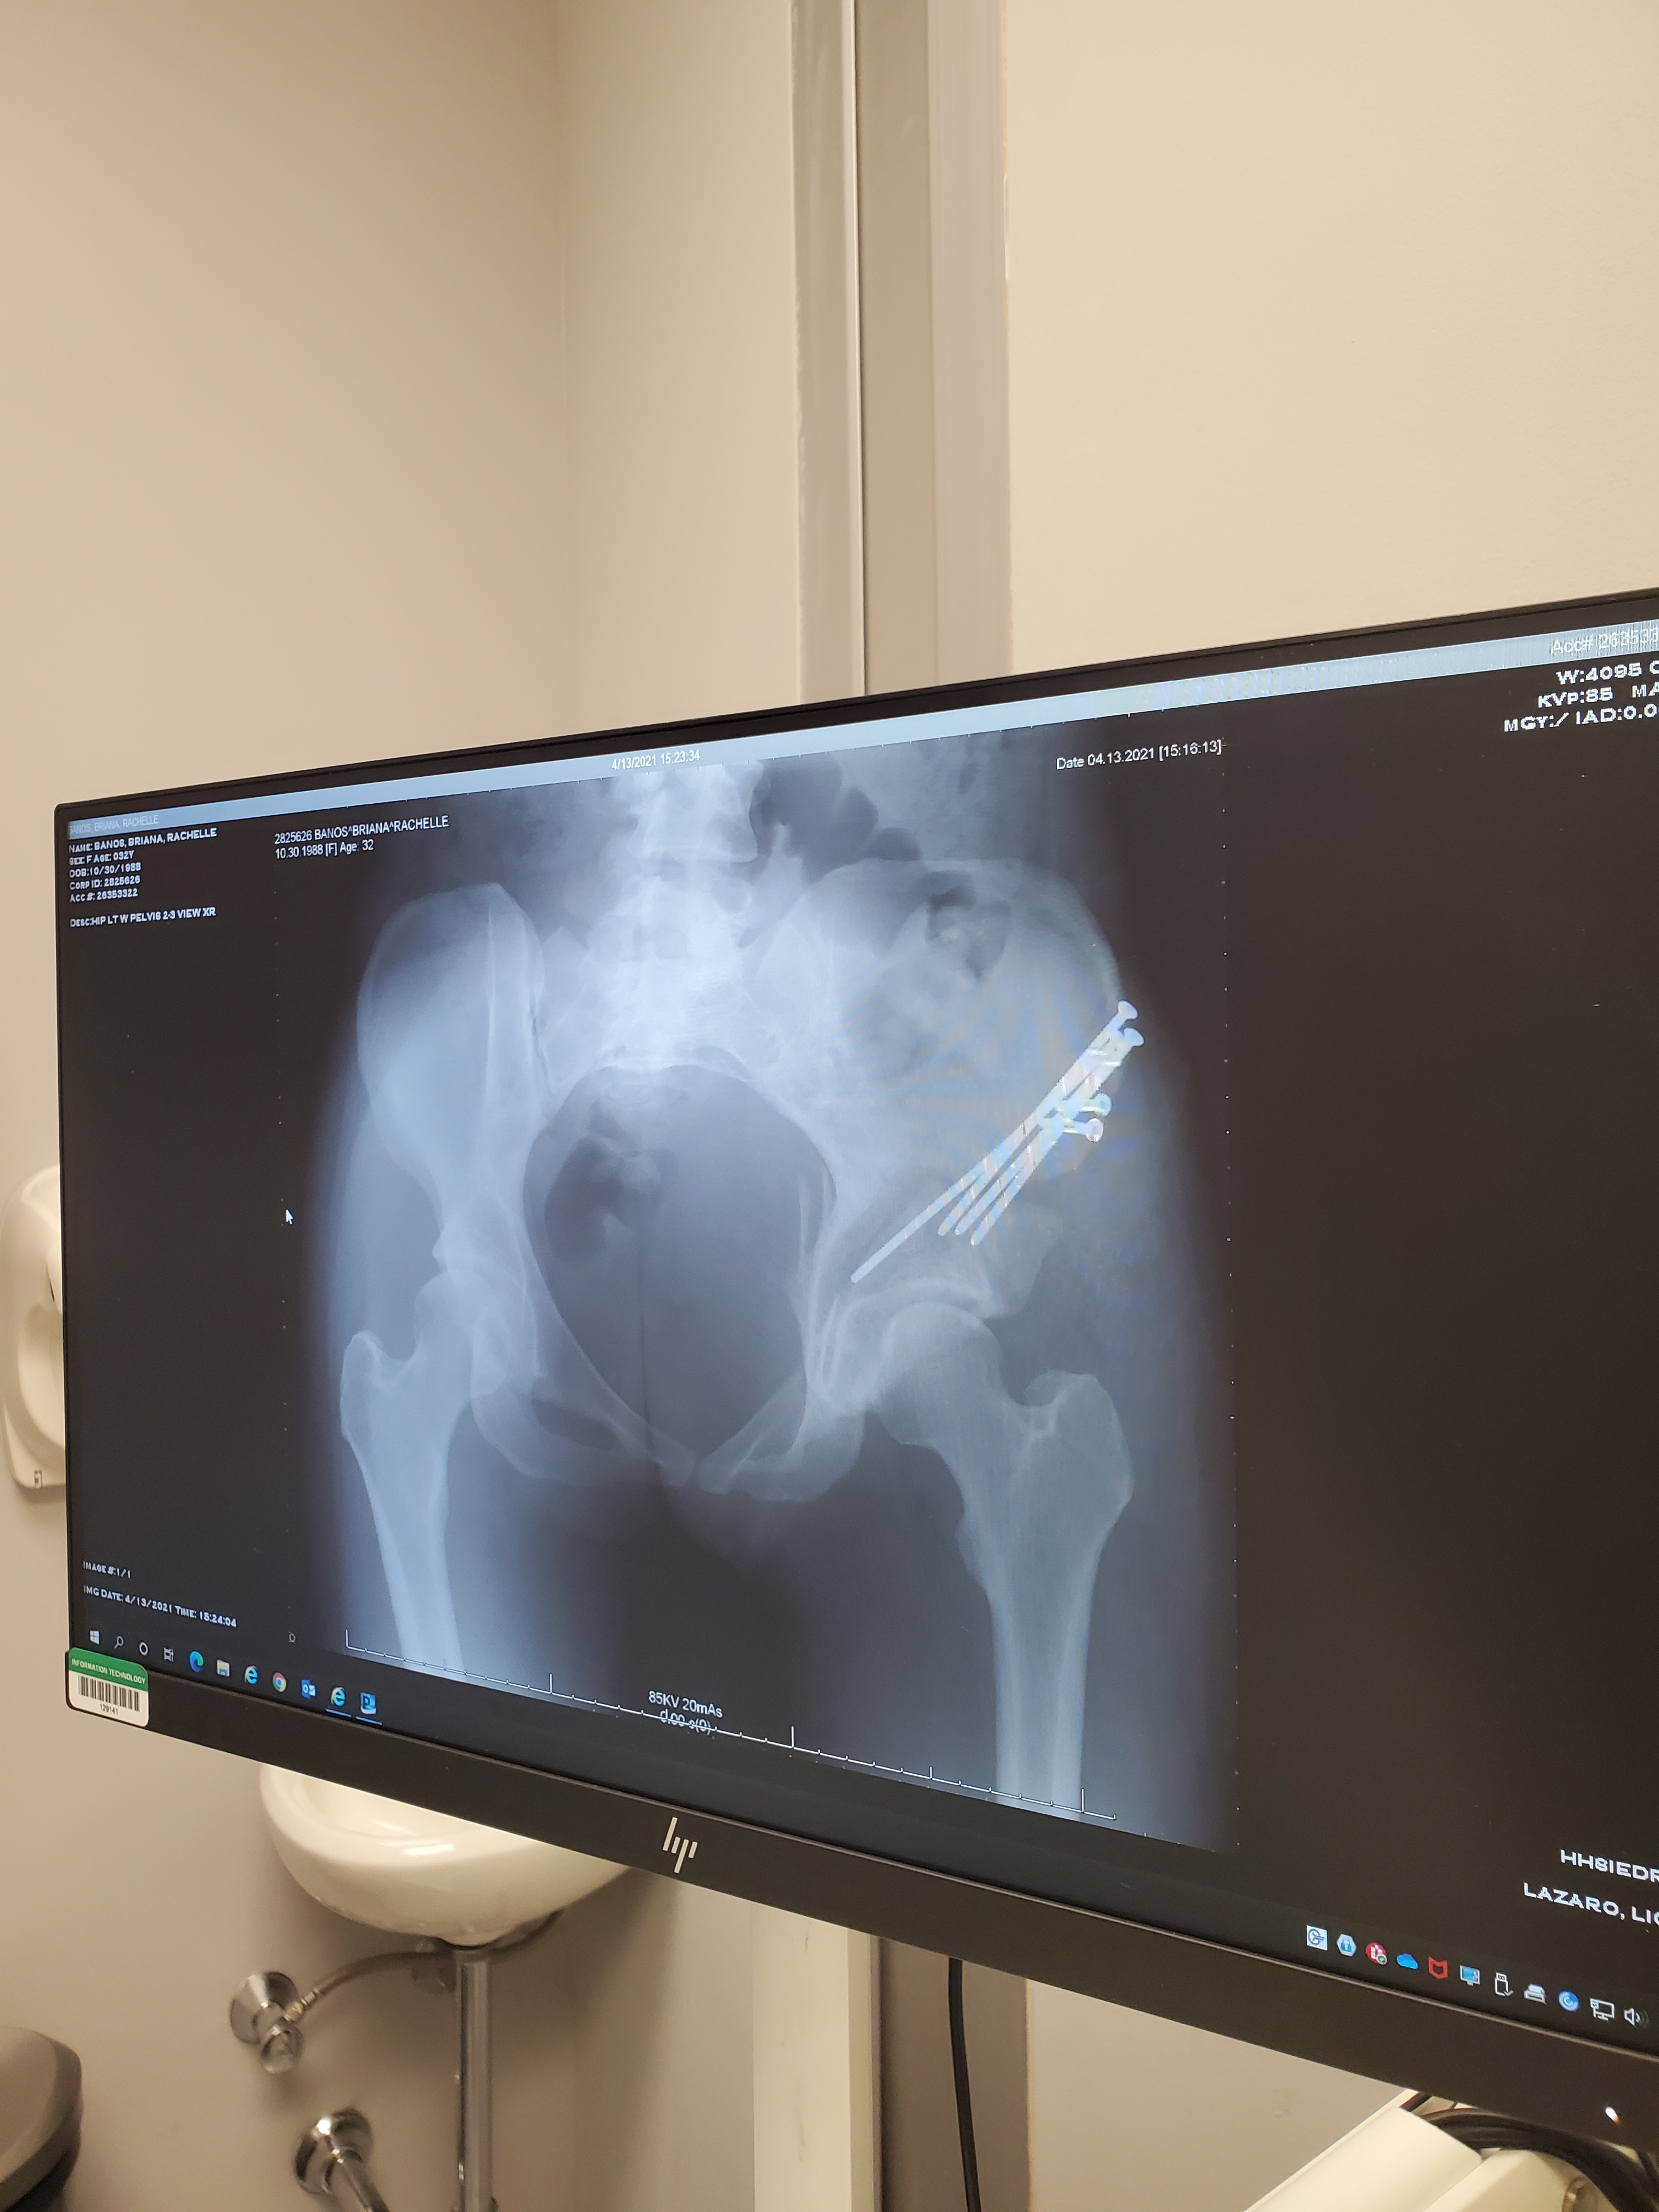

It’s now been 5 weeks since my first arthroscopy surgery and 3 weeks since my PAO surgery.

But let’s cut to the chase… who wants to see the money pics!! Screws and all!